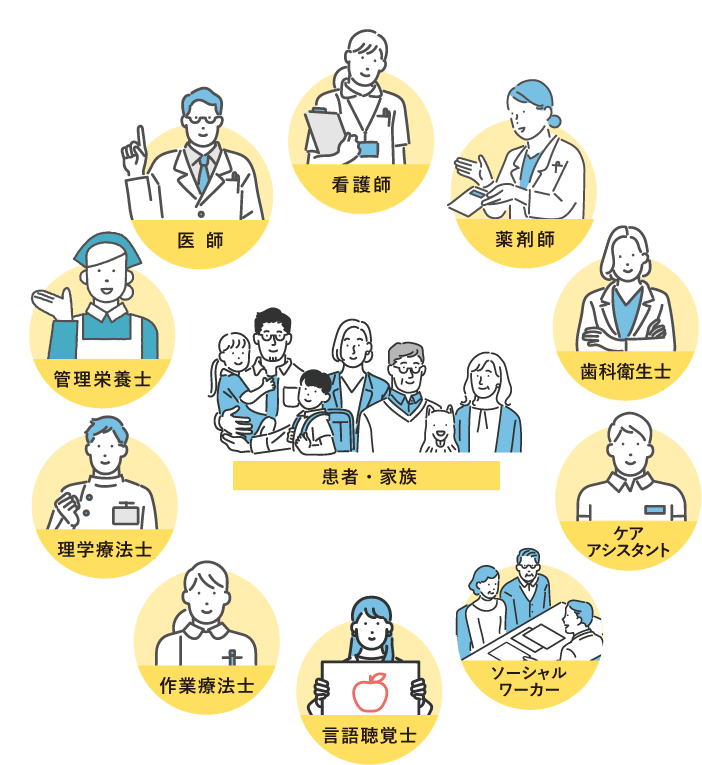

整形外科の救急医療・急性期治療を中心に、地域包括ケア、 回復期リハビリテーション、さらには緩和ケアと様々な分野の医療に取り組んでいます。

在宅復帰を目指し、地域医療へ貢献するため、病病連携・病診連携に取り組み、多職種連携を行い、全人的医療の実践を行っています。

脆弱性骨折は繰り返すことが多く、二次性骨折を予防することは極めて重要と考え、骨粗鬆症の治療にも力を入れています。種々の骨代謝マーカーの測定や高解像度末梢骨用定量的コンピュータ断層撮影装置(HR-pQCT)撮影も可能で、骨の微細構造を明らかにし、必要時には実際の治療に取り入れています。多職種(医師、看護師、社会福祉士、薬剤師、管理栄養士、理学療法士、作業療法士、言語聴覚士など)によるチーム医療を積極的に構築し、各職種の専門性を重視した診療を行っています。